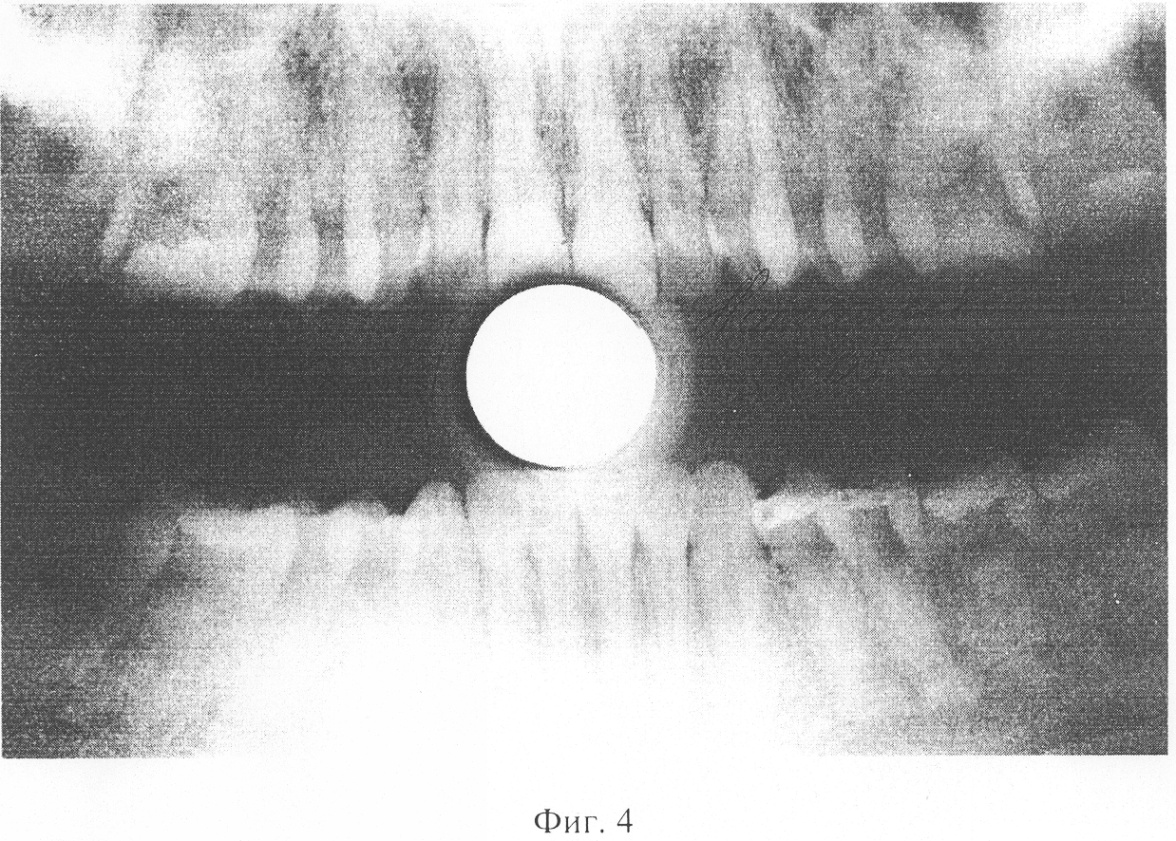

на фиг.4 – панорамный дентальный рентгеновский снимок, полученный на прицельно-панорамном аппарате «ПАРДУС»

На фиг.3 и фиг.4 представлены два снимка – полученный на аппарате с протяженным фокусным пятном (0.7 мм в диаметре, фиг.3) и полученный на микрофокусном аппарате (менее 0.1 мм в диаметре, фиг.4).

Снимки отсканированы таким образом, что их разрешение составляет 1500×1000 пикселей притом, что исходный размер составлял 300 на 200 мм. Ввиду примерной одинаковости видимых размеров деталей на снимках возможно их корректное сравнение.

Проведенный по формуле (3) анализ дал следующие результаты: Q для снимка с протяженным фокусным пятном составляет 15, а Q для снимка на микрофокусном источнике составляет 530.

В соответствии с заявляемым способом было проведено сравнение 8 снимков, полученных на аппарате с протяженным фокусным пятном, и 7 – на микрофокусном источнике. Среднее значение Q для традиционных снимков составило 12,5 при разбросе значений от 9 до 26, среднее значение для микрофокусных снимков составило 462,4 при разбросе значений от 380 до 625.